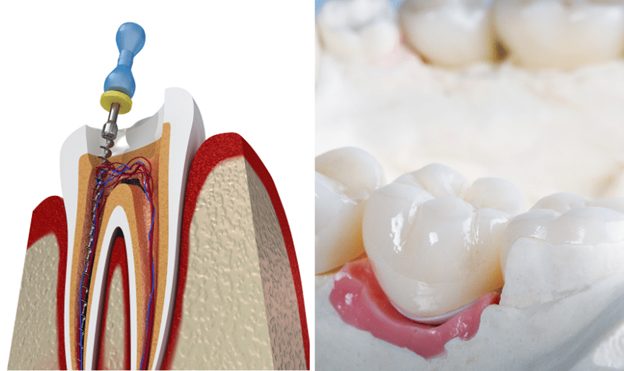

درمان ریشه به یک روش دندانپزشکی اشاره دارد که در آن پالپ عفونی، لایه داخلی دندان که شامل اعصاب و عروق خونی است، برداشته می شود. این عفونت می تواند ناشی از پوسیدگی عمیق، ترک خوردگی دندان یا فرایندهای دندانپزشکی روی همان دندان باشد.

دندانپزشک در طول درمان ریشه، ناحیه اطراف دندان را بی حس می کند، یک حفره کوچک در تاج ایجاد می کند و پالپ عفونی را با دقت خارج می کند. سپس داخل دندان قبل از پر شدن با ماده مخصوص تمیز و ضد عفونی می شود. گاهی اوقات، ممکن است برای بازیابی قدرت و عملکرد آن، یک روکش روی دندان قرار داده شود.